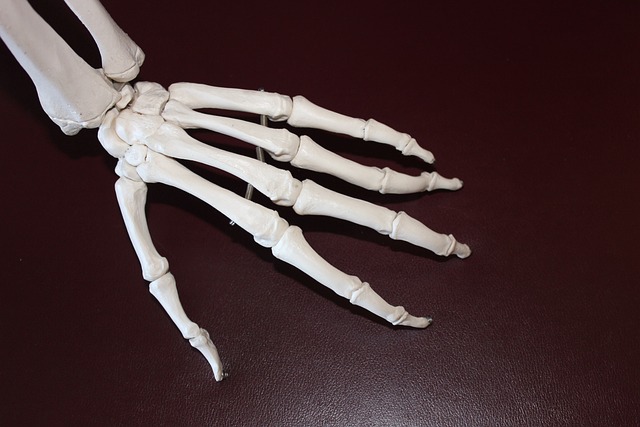

팔 관절

- 어깨 관절: 팔과 체간을 연결하는 가장 큰 관절

- 팔꿈치 관절: 상완골과 전완골을 연결하는 관절

- 손목 관절: 전완골과 손을 연결하는 관절

- 손가락 관절: 손가락 뼈들을 연결하는 관절

손목 관절 및 손가락 관절

- 아연: 관절 연골 생성과 면역력 강화

- 보론: 관절 염증 감소와 관절 가동성 개선